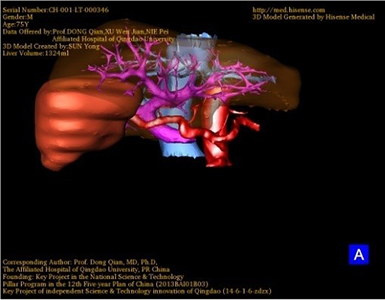

胆管细胞癌-CH-001-LT-000346

一般情况:CH-001-LT-000346,74岁男性患者。

将0.625mm双源薄层CT资料的静脉期和动脉期Dicom格式文件导入海信CAS系统。

通过调节窗宽窗位调整CT序号,对肿瘤,肝实质,胆囊,下腔静脉,肿瘤,肝动脉、门静脉及肝静脉等进行三维重建;系统自动计算肿瘤体积和肝脏体积。(图2—截图1---后链接截图2)

模拟手术操作,自动计算切除肿瘤体积。肝脏体积为1324ml,肿瘤体积为286.1ml,肿瘤体积为肝脏体积的21.6%,通过比对70-80岁正常肝脏体积为1118.08±190.14ml,通过术前模拟手术,精准判断切除后剩余肝脏体积能耐受,避免肝衰竭发生。术前手术方案的规划。

术前三维重建:

重建图片